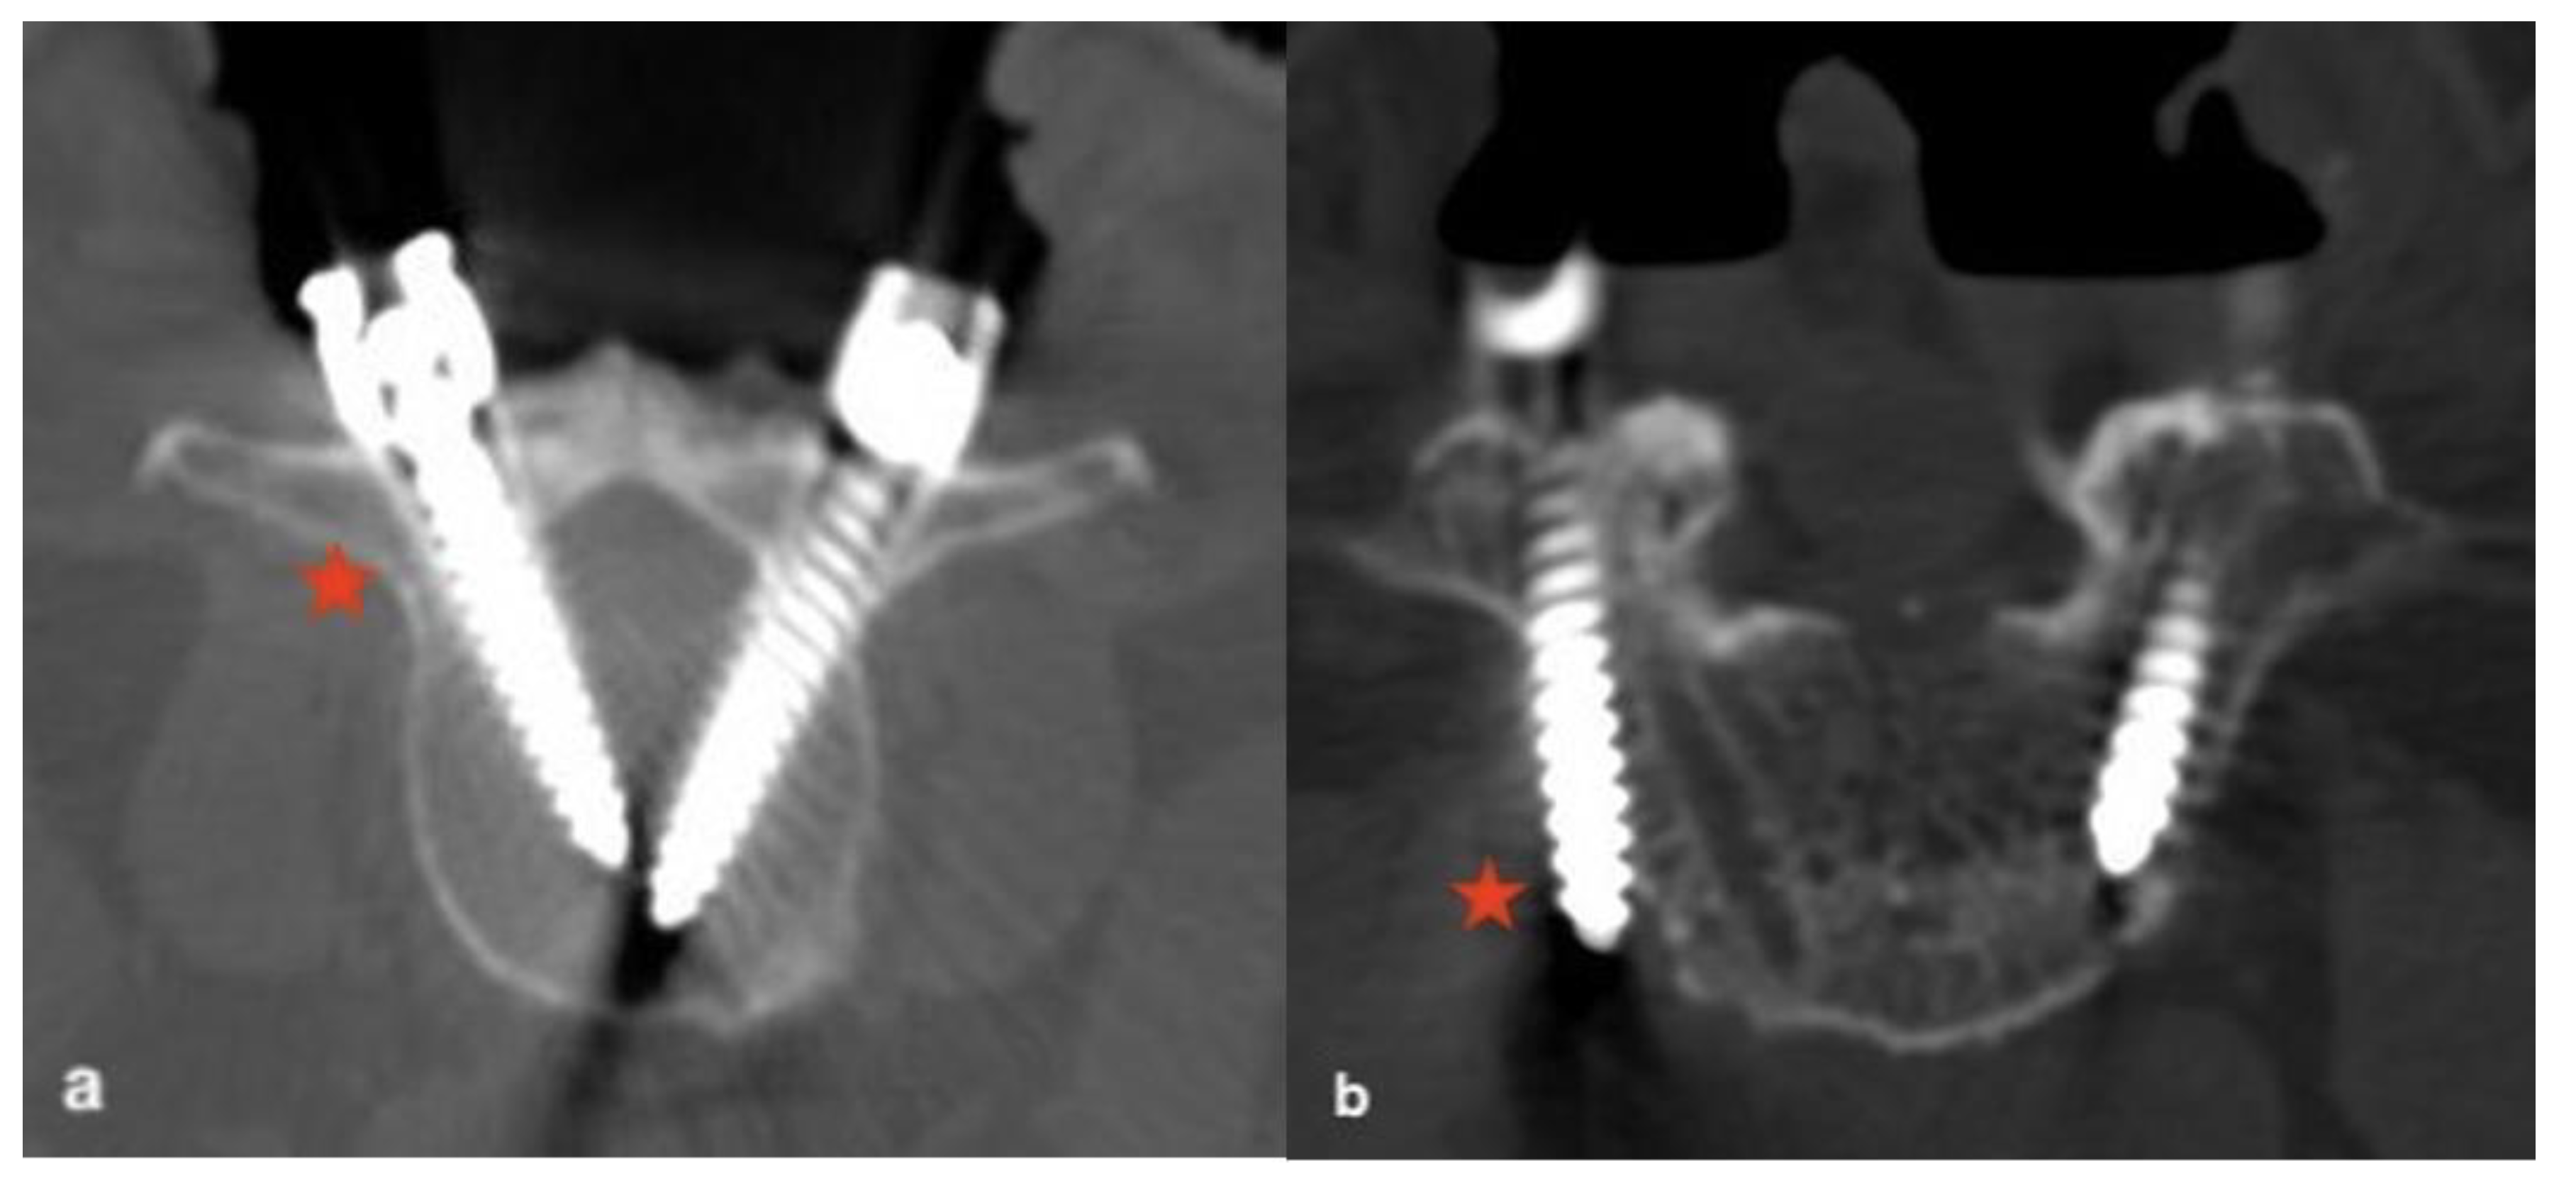

2.2. Assessment of TPS Placement

2.3. Radiographic and Clinical Analyses